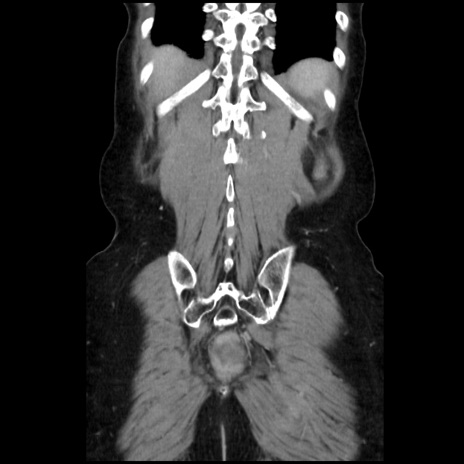

症例32(冠状断像)

【症例】40歳代 女性

【主訴】上腹部痛、嘔気・嘔吐

【現病歴】約9時間前頃から急に上腹部痛、嘔気、嘔吐が出現。改善しないため救急要請。

【既往歴】子宮頚癌(広汎子宮全摘術、放射線療法)、腸閉塞

【身体所見】腹部:平坦、軟、腸雑音亢進、上腹部を中心に腹部全体に圧痛あり。

【データ】WBC 8400、CRP 0.03